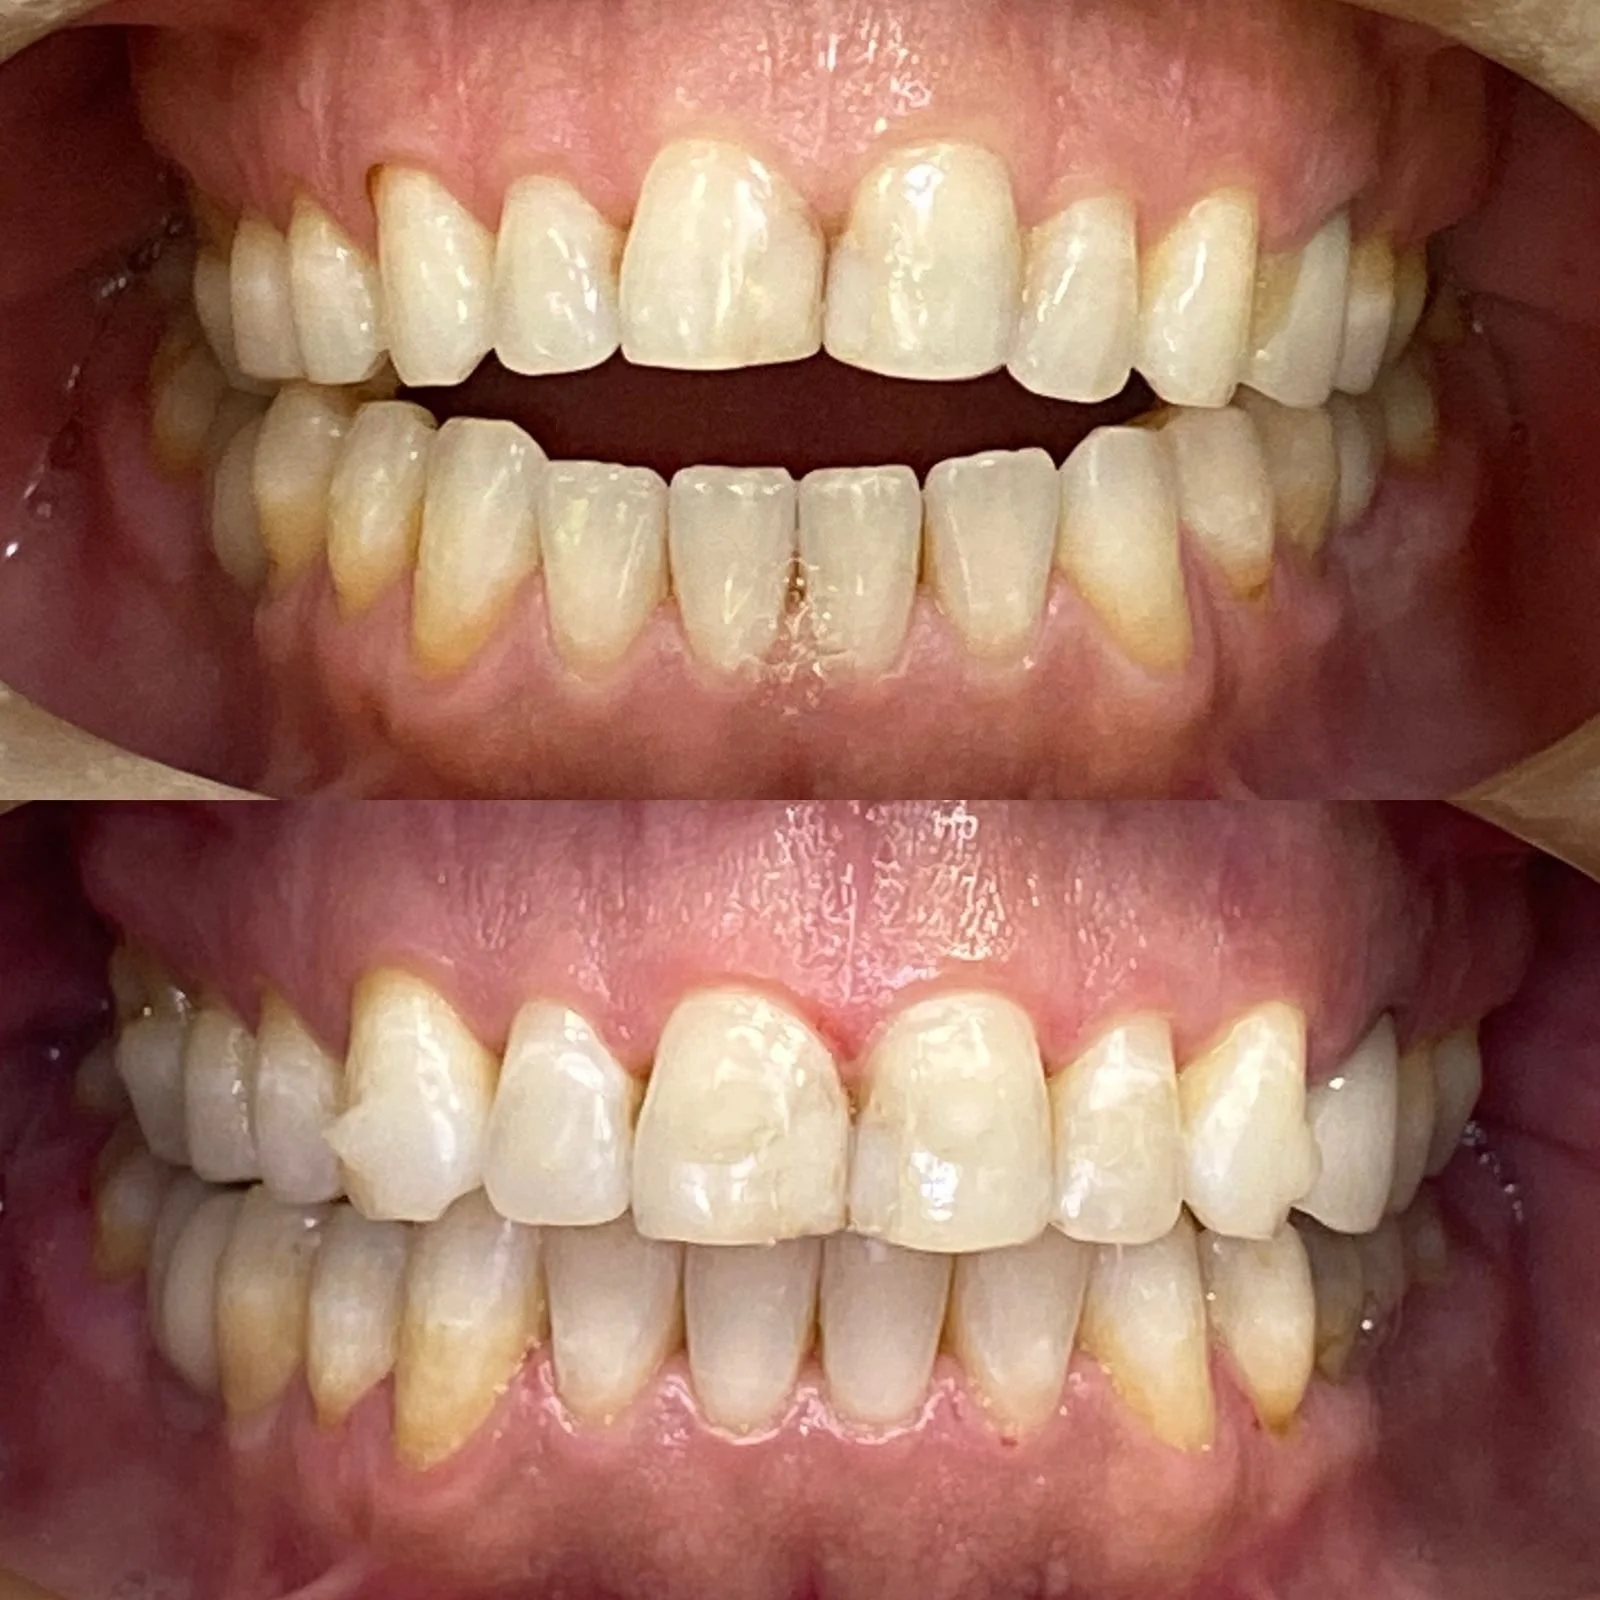

Somos duas dentistas, apaixonadas por transformar sorrisos e melhorar a autoestima dos nossos clientes. Prezamos por um trabalho acolhedor, individualizado, feito com muita ética e responsabilidade.